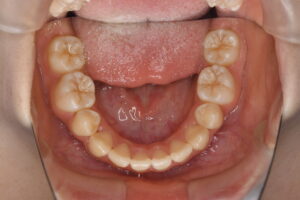

実際の症例紹介(20代女性/裏側ワイヤー矯正)

治療前

治療後

・主訴:八重歯と前歯の突出

・治療法:裏側からのワイヤー矯正(リンガル)

・治療期間:約1年半〜2年(目安)

・予想される副作用・リスク:装置装着後の違和感・疼痛、発音のしづらさ、一時的な咀嚼効率低下、ブラッシング不良によるむし歯・歯周病リスク など

※写真は代表的な症例です。口腔内の状態により治療法や期間は異なります。詳細は初診相談でご説明します。